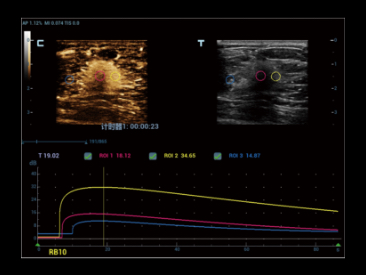

Dzi?ki technologii ZST+oraz Plane Waves, funkcja HiFR CEUS umo?liwia ultraszybk? wizualizacj? struktury naczyniowej i charakteru perfuzji w fazie t?tniczej.; mo?e s?u?y? jako narz?dzie uzupe?niaj?ce dla funkcji?UWN+

Przypadek kliniczny z wykorzystaniem technologii HiFR CEUS: Ogniskowy rozrost guzkowy w?troby

*?Nie zaleca si? stosowania HiFR CEUS w fazie p├│?nej lub na g??boko?ci 10 cm